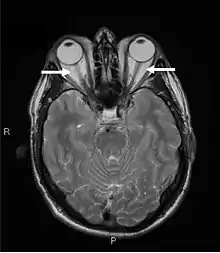

Серцево-судинні розлади: відчуття серцебиття в спокої, прискорення пульсу понад 100 уд/хв, збільшення щитоподібної залози (зоб), підвищення обміну речовин, зокрема основного обміну (тобто посилене споживання кисню), збудження, тремтіння рук, пітливість, схуднення на 10-15 кг та більше, підвищений апетит, екзофтальм (випинання очей), зниження якості життя.[1]